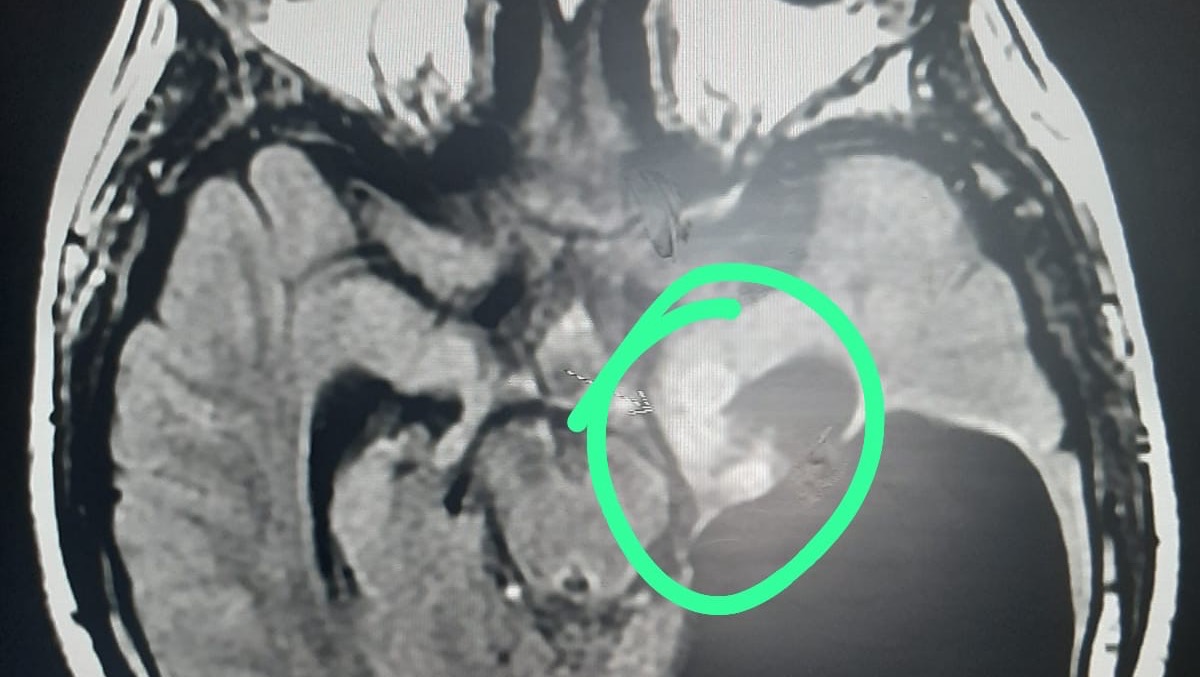

Adriano was detected with a brain tumor on the left occipital side when he was barely 3 years old, today he is 11 years old and we continue in this hard battle.

In all this time they have already performed 4 cranioctomies (brain operations) to be able to remove the tumor but it grows again behaves aggressively, expands and became recurrent, this time it was not only on the left occipital side, also in the hypothalamus and in the ventricles of the brain, this has been accompanied by daily repetitive convulsions, delay of psychomotor development, among other sequelae caused by the tumor and the operations already performed.

On February 17 we were able to admit him to a hospital and they sent us an MRI which with a lot of effort we were able to perform, the neurosurgeon was able to read the images and has asked us again for another MRI to see the growth of the tumor and has referred him to the oncologist so that he can give the appropriate treatment since he is only in charge of the surgical part and the oncologist of the chemotherapy and radiotherapy treatment, and he determines how many sessions he needs, but this is very expensive and that is why I come with all my heart to ask for your support.